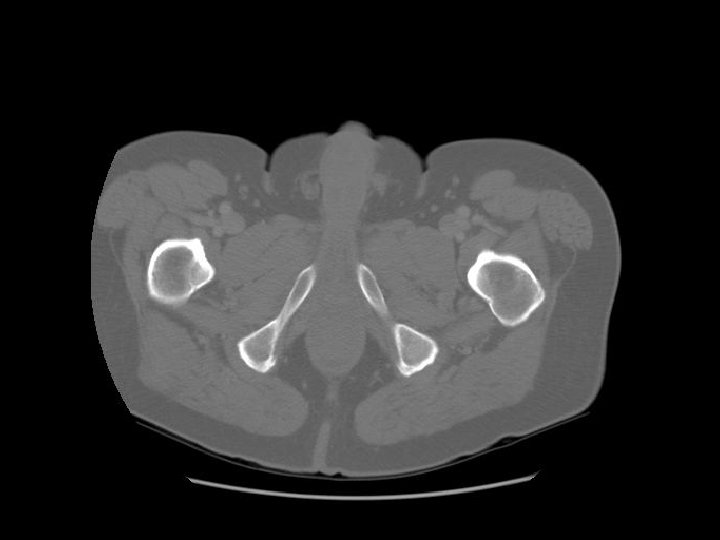

Femoral artery Femoral vein

Femoral head Acetabulum

Ischiorectal fossa

Shaft of penis

Femur